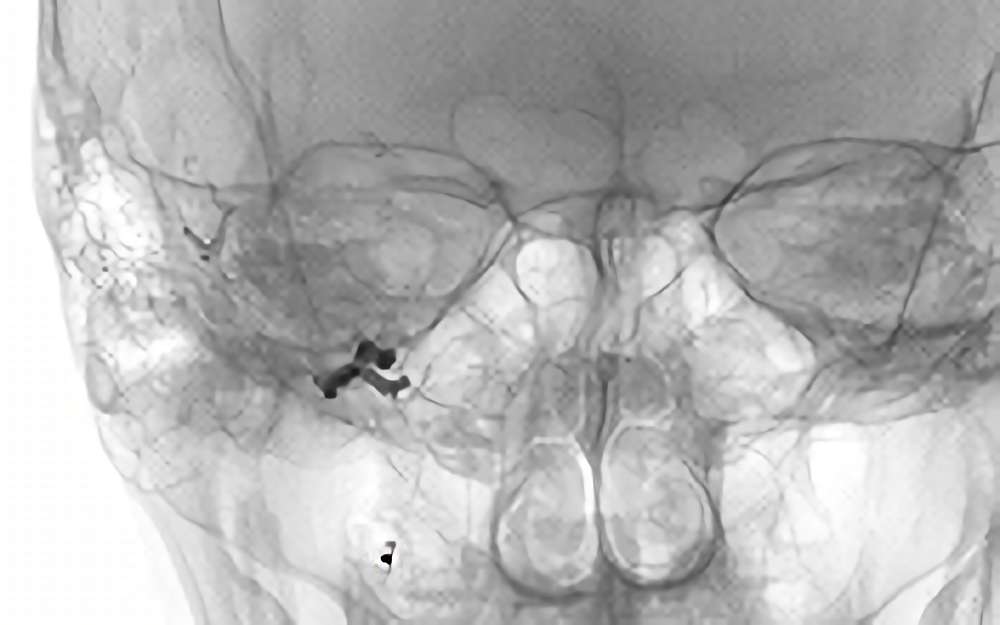

No.1583 手術前

No.1583 手術中

No.1583 手術後